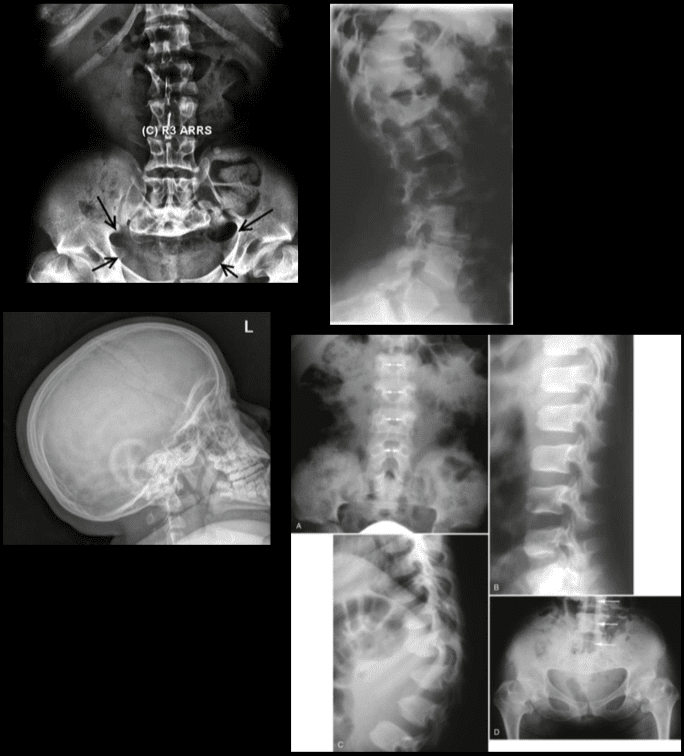

Studji dwar l-Immaġini

L-immaġini f'mard deġenerattiv tad-diska tintuża prinċipalment biex tiddeskrivi relazzjonijiet anatomiċi u karatteristiċi morfoloġiċi tad-diski affettwati, li għandha valur terapewtiku kbir fit-teħid ta 'deċiżjonijiet futuri għal għażliet ta' trattament. Kwalunkwe metodu ta 'immaġini, bħal radjografija sempliċi, CT, jew MRI, jista' jipprovdi informazzjoni utli. Madankollu, kawża sottostanti tista 'tinstab biss fi 15% tal-pazjenti billi l-ebda bidliet radjoloġiċi ċari ma huma viżibbli f'mard deġenerattiv tad-diska fin-nuqqas ta' ħernja tad-diska u defiċit newroloġiku. Barra minn hekk, m'hemm l-ebda korrelazzjoni bejn il-bidliet anatomiċi li dehru fuq l-immaġini u s-severità tas-sintomi, għalkemm hemm korrelazzjonijiet bejn in-numru ta 'osteofiti u s-severità ta' uġigħ fid-dahar. Bidliet deġenerattivi fir-radjografija jistgħu jidhru wkoll f'nies bla sintomi li jwasslu għal diffikultà biex jikkonformaw ir-rilevanza klinika u meta tibda l-kura. ("Marda tad-Diska Deġenerattiva" Fiżjopedja)

Modic iddeskriva l-bidliet li jseħħu fil-korpi vertebrali li jmissu mad-diski li jiddegeneraw bħala bidliet tat-Tip 1 u tat-Tip 2. Fil-bidliet Modic 1, hemm tnaqqis fl-intensità ta 'immaġini ppeżati T1 u żieda fl-intensità ta' immaġini ppeżati T2. Dan huwa maħsub li jseħħ minħabba li l-pjanċi tat-tarf għaddew minn sklerożi u l-mudullun li jmissu qed juri rispons infjammatorju hekk kif il-koeffiċjent ta 'diffużjoni jiżdied. Din iż-żieda ta 'koeffiċjent ta' diffużjoni u r-reżistenza aħħarija għad-diffużjoni hija kkawżata mis-sustanzi kimiċi rilaxxati permezz ta 'mekkaniżmu awtoimmuni. Il-bidliet modiċi tat-tip 2 jinkludu l-qerda tal-mudullun ta 'l-endplates vertebrali biswitha minħabba rispons infjammatorju u l-infiltrazzjoni ta' xaħam fil-mudullun. Dawn il-bidliet jistgħu jwasslu għal żieda fid-densità tas-sinjal fuq immaġini ppeżati T1. (Modic, MT et al.)

Tomografija Kompjuterizzata (CT)

Meta l-MRI ma tkunx disponibbli, it-tomografija bil-kompjuter hija meqjusa bħala test dijanjostiku li jista 'jikxef il-herniation tad-diska minħabba li għandu kuntrast aħjar bejn il-marġini posterolaterali tal-vertebri tal-għadam li jmissu magħhom, ix-xaħam perineali u l-materjal tad-diska hernjata. Anke hekk, meta tiddijanjostika l-herniations laterali, l-MRI tibqa 'l-modalità tal-immaġini magħżula.

Is-CT scan għandu bosta vantaġġi fuq l-MRI bħal ma għandu ambjent inqas klaustrofobiku, bi prezz baxx, u skoperta aħjar ta 'bidliet fil-bonny li huma sottili u li jistgħu jitilfu fuq modalitajiet oħra. CT jista 'jinduna bidliet deġenerattivi bikrija tal-ġonot tal-faċċata u spondilosi b'aktar eżattezza. L-integrità tal-għadam wara l-fużjoni hija wkoll l-iktar evalwata minn CT.

Il-herniation disk u l-imġieba tan-nervituri assoċjati jistgħu jiġu djanjostikati bl-użu tal-kriterji żviluppati minn Gundry u Heithoff. Huwa importanti li l-isporġenza tad-diska tkun direttament fuq l-għeruq tan-nervituri li jaqsmu d-diska u tkun fokali u asimmetrika b'pożizzjoni dorsolaterali. Għandu jkun hemm kompressjoni jew spostament tal-għeruq tan-nervituri dimostrabbli. Fl-aħħar, in-nerv distali għall-imblokk (sit ta 'l-herniation) ħafna drabi tkabbar u ttaffi bl-edema li tirriżulta, prominenza ta' vini epidurali adjaċenti, u exudati infjammatorji li jirriżultaw fit-tiċpir tal-marġni.